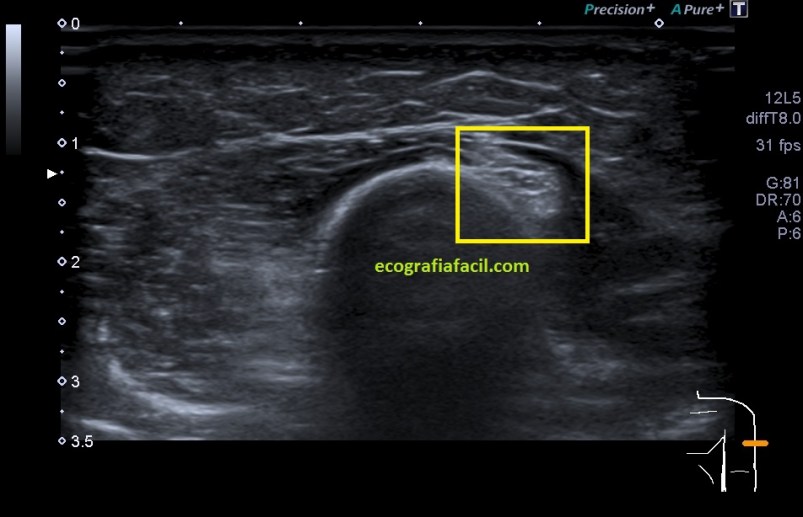

Durante la exploración del hombro me encontré un hallazgo que bien por la experiencia o por la intuición, quizá ambas, busco en cada protocolo de hombro que hago y que es punto de dolor irradiado habitual del hombro justo donde el radial pasa por la parte posterior del húmero antes de buscar la cara antero lateral externa del codo, encontrándome estas imágenes que te comento semiológicamente y que son típicas de neuropatía.

En el lugar comentado anteriormente, encuentro una estructura hipoecogénica que no es compatible con la normalidad de un nervio, como si lo es la imagen 6A que te enseño a continuación donde el nervio radial contralateral te dice cómo es un nervio radial normal en el mismo punto que el de la imagen 6, mira:

El corte longitudinal del nervio afectado es muy llamativo, tanto en su aspecto ecográfico como en su tamaño y puedes verlo en las imágenes 7 y 8.